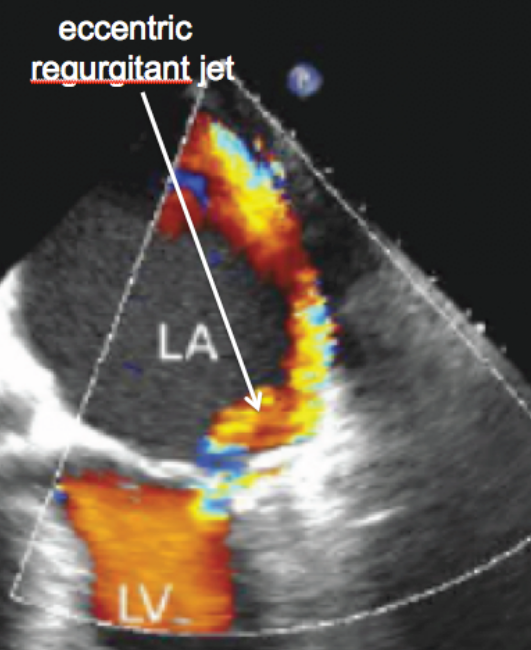

We consider the flow of an incompressible fluid through a planar channel with a narrowing, where the walls creating the narrowing have variable curvature. An application that motivated the present study is the flow of blood through a regurgitant mitral valve. Mitral regurgitation (MR) is a valvular disease characterized by abnormal leaking of blood through the mitral valve from the left ventricle into the left atrium of the heart. See Fig. 1. In certain cases, the regurgitant jet “hugs” the wall of the heart’s atrium as shown in Fig. 1 (right). These wall-hugging, non-symmetric regurgitant jets have been observed at low Reynolds numbers (Vermeulen et al. (2009); Albers et al. (2004)) and are said to undergo the Coanda effect (Wille and Fernholz (1965)). Such jets represent one of the biggest challenges in echocardiographic assessment of MR (Ginghina (2007)). In (Quaini et al. (2016); Pitton et al. (2017); Pitton and Rozza (2017); Wang et al. (2017); Hess et. al. (2018); Hess et al. (2018)), we made a connection between the cardiovascular and bioengineering literature reporting on the Coanda effect in MR and the fluid dynamics literature with the goal of identifying and understanding the main features of the corresponding flow conditions.

Figure 1: Left: Anatomy of the heart showing the mitral valve. Right: Echocardiographic image of a jet flowing from the left ventricle (LV) to the left atrium (LA) hugging the walls of the LA. Colors denote different fluid velocities.